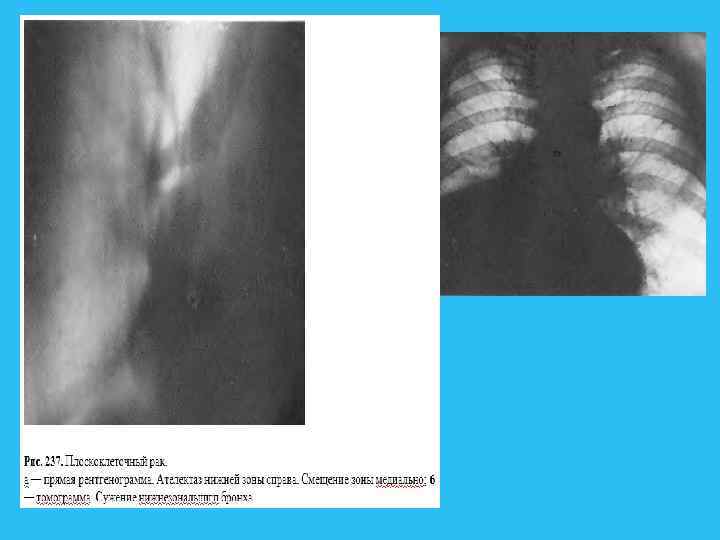

Рис 229. Ателектаз переднего сегмента верхней доли слева. а — прямая рентгенограмма; 6 — боковая томограмма. Сужение устья переднесегментарного бронха.

Ателектазы при раке бывают, как правило, осложненными, что в основном объясняется их длительным существованием. При наступившей обтурации бронха достаточно несколько часов для того, чтобы воздух в аль веолах рассосался и сегмент спался. В спавшемся участке легкого действие эластичной тяги приводит к расширению бронхов, калибр и состояние которых влияют на степень эффекта расширения. Более крупные бронхи с выраженными хрящевыми кольцами расширяются в меньшей степени, чем мелкие. Просвет последних увеличивается еще в большей степени, если стенки их изменены под влиянием перенесенной инфекции. Появляется функциональная неполноценность бронхов, в их просвете накапливаются слизь и мокрота. Измененные стенки бронхов оказываются нечувствительными к накапливающейся мокроте и нормальный кашлевой рефлекс на небольшие порции содержимого не возникает. В этих случаях, даже несмотря на частично сохранившуюся проходимость дренирующего бронха, очищения воздухоносных путей от секрета не происходит, что приводит к дополнительной закупорке просвета бронха и полному прекращению вентиляции. Кроме расширения бронхов, в зоне ателектаза наступает расширение не только артерий, но и вен, прекапилляров и капилляров. Происходит увеличение кровенаполнения и насасывание жидкости в альвеолы. В спавшемся отделе легкого рано или поздно возникает воспалительный процесс. Нарушение эластичности стенок бронха препятствует вос становлению нормальных физиологических условий и развитие хронического легочного нагноения становится неизбежным. Рентгенологические проявления трех стадий нарушения вентиляции обусловлены совокупностью анатомических и функциональных факторов, а также особенностями образования рентгенологической тени.

Немалое значение в правильной расшифровке рентгенограмм имеет знание закономерностей перемещения отдельных зон и сегментов при их спадении. Закономерности спадения долей представлены на рис. 234. Рис. 234. Схема спадений долой при ателектазах (по Anacker, 1063). а — верхняя доля; 6 — Средняя доли и язычок; в — нижняя доля.